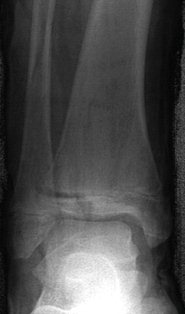

- Ankle injuries - the "mortise view" is much more useful than the standard AP. This is an AP projection taken with the leg internally rotated by 20 -30 degrees to demonstrate the joint surfaces without overlap by the distal fibula.

| Figure 28: X-ray and CT scan of triplane fracture |